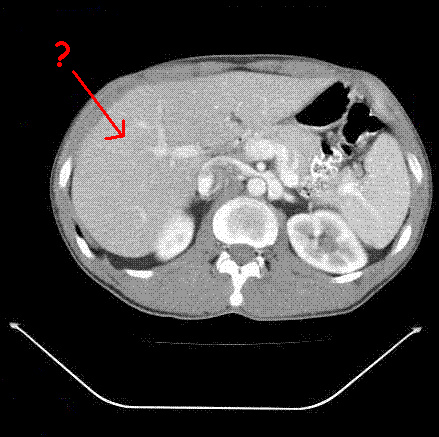

What structure is this?

This structure is the liver.

In relationship to the kidney, the liver falls where anatomically?

The liver is anterior and superior of the kidneys.